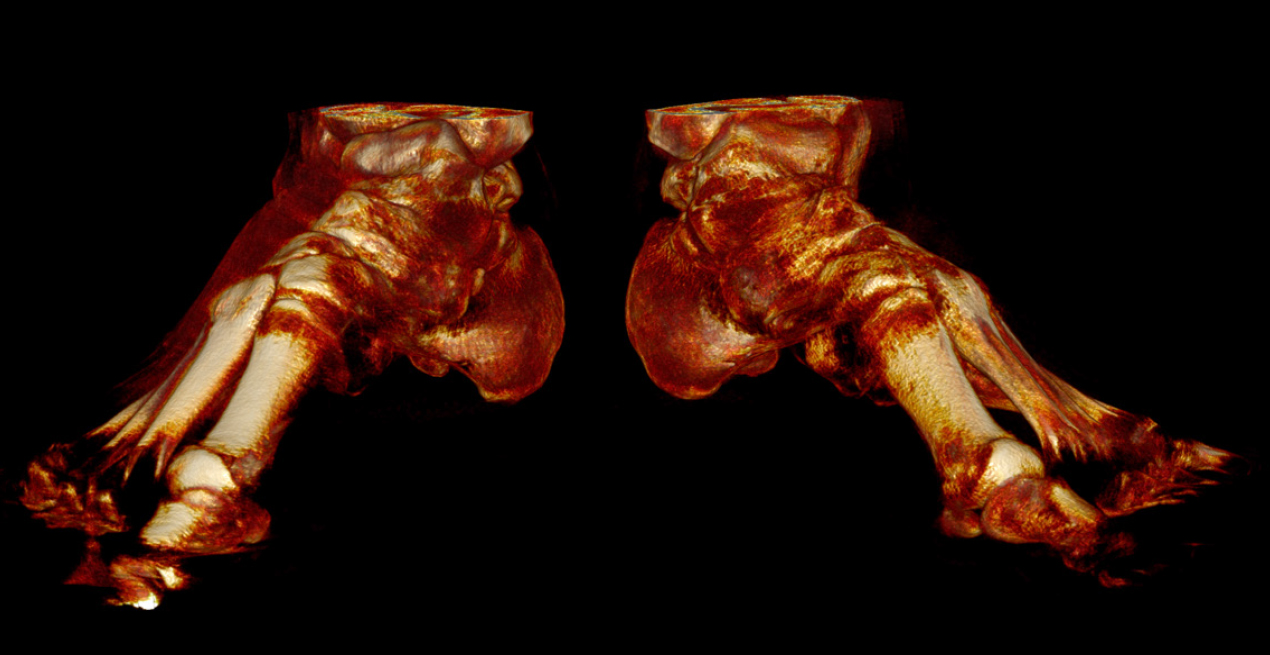

ATRISS — a compact modern weight-bearing CT system offers a new method for obtaining 3D-images of the foot and ankle joint in an upright position under natural load.

- Examination of mutual position of the foot joints and ankle joint under natural load

- Examination of patients with flat feet in the upright position with determining true foot bones parameters